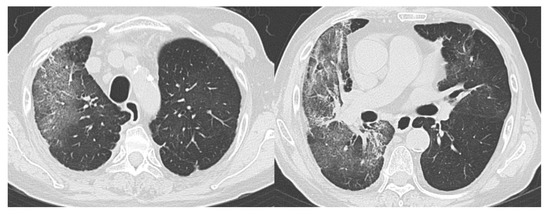

- CO-RADS 5 means a very high level of suspicion for pulmonary lesion resulting from COVID-19, based on typical CT findings. Obligatory features are ground-glass opacities, with or without consolidations, close to visceral pleural surfaces, including the fissures, and a multifocal bilateral distribution.